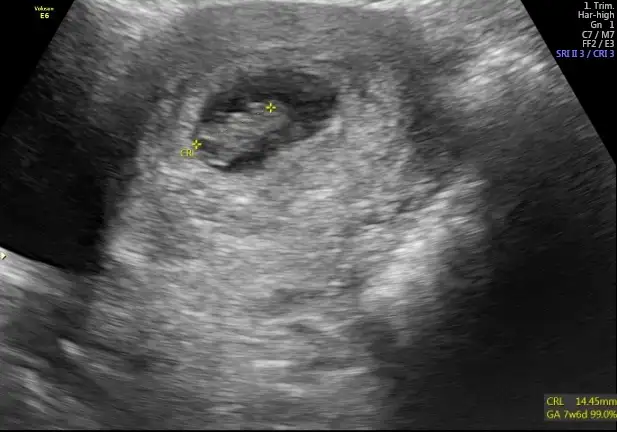

IMG_20170314_234430~2.webp IMG_20170314_234443~2.webp IMG_20170324_132819.webp

Merhabalar bende bı tahmin alabilirmiyim acaba 7. Hafta 10.hafta ve 12.hafta ultrason fotolarina bakarmisiniz benim ikinci bebeğim kızımın ultrason fotolarina bakıyorum bu bebeğim çok farklı acaba cinsiyet farklimi ki nuba göre bakıyorum ama anlayamadım bi anlayan arkadaşlardan rica ediyorum